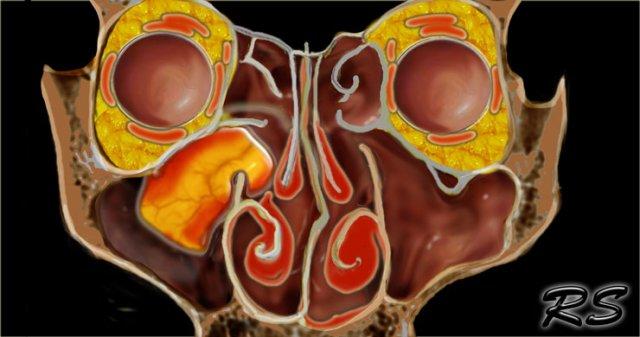

Ca bệnh minh họa này thể hiện rõ nét hình ảnh nang nhầy hai bên.

Bệnh nhân này có viêm xoang mạn tính với mờ đục toàn bộ xoang mũi, ứ đọng dịch nhầy trong các xoang hàm và nang nhầy hai bên kích thước lớn.

CT cho thấy tăng tỷ trọng và MRI cho thấy tăng tín hiệu trên chuỗi xung T2W – cả hai đều là dấu hiệu lành tính trong bệnh lý mũi xoang, gợi ý chất dịch giàu protein.

Có hình ảnh tái cấu trúc xương trơn láng và đẩy lồi thành xoang trán; mặc dù trông như có phá hủy xương tại ranh giới hốc mắt của xoang trán, nhưng thông thường phẫu thuật viên vẫn có thể quan sát thấy một lớp xương mỏng còn nguyên vẹn tại chỗ.